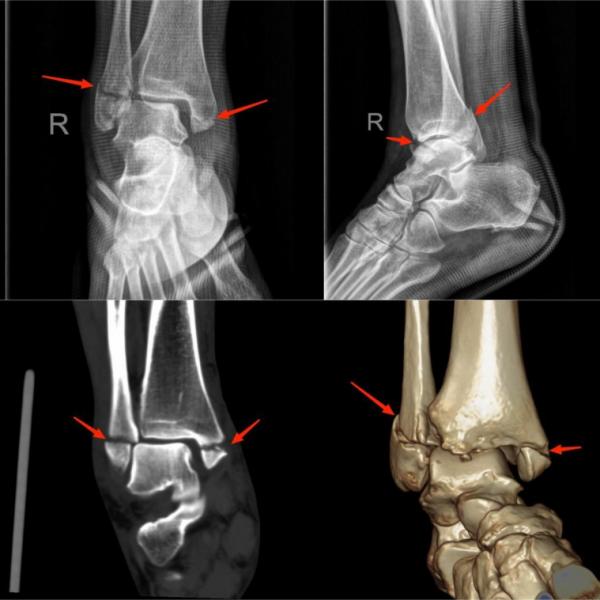

(上图为右踝关节内、外踝骨折)

常见原因:在运动过程中受力不当诱发,当足踝的关节超过正常的活动范围内,它周围的结构就会受到牵拉,从而会出现一些撕裂伤,如外踝撕脱骨折。